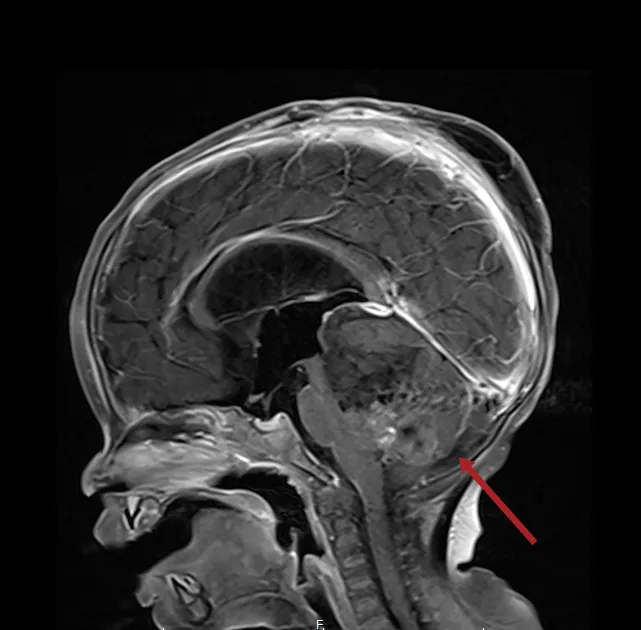

在診斷方面,醫師會先透過病史詢問與神經學檢查評估,再安排影像檢查,如電腦斷層(CT)或核磁共振(MRI),確認腫瘤位置與大小,必要時再進一步做腦血管檢查。治療則以手術切除為主,搭配放射線或化學治療。像口服化療藥物Temozolomide已成為常見第一線用藥,可延長患者存活期;另外也有標靶藥物與免疫療法作為後續選擇。

國泰醫院指出,腦瘤預後與腫瘤種類、位置及治療方式密切相關,部分良性腫瘤可完全治療,但惡性腦瘤整體預後仍不佳,平均存活期約15個月,最嚴重類型5年存活率僅約5%。因此強調「早期發現、及早治療」是關鍵,治療後也需定期追蹤。隨著基因檢測與新療法發展,未來有機會提升治療效果,但現階段仍須提高警覺,出現異常症狀應儘早就醫。